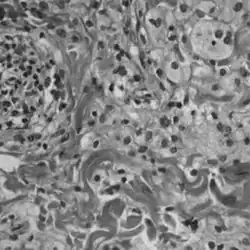

Choroba Erdheima-Chestera (ang. Erdheim-Chester disease, Erdheim-Chester syndrome, polyostotic sclerosing histiocytosis) – rzadka postać histiocytozy nie wywodzącej się z komórek Langerhansa. Początek choroby przypada zazwyczaj na wiek średni (średnia wieku zachorowania to 53 lata[1]). W przebiegu choroby obserwuje się nacieki z obładowanych lipidami makrofagów, wielojądrowe komórki olbrzymie i naciek zapalny z limfocytów i histiocytów w szpiku kostnym, a także uogólnione stwardnienie kości długich.